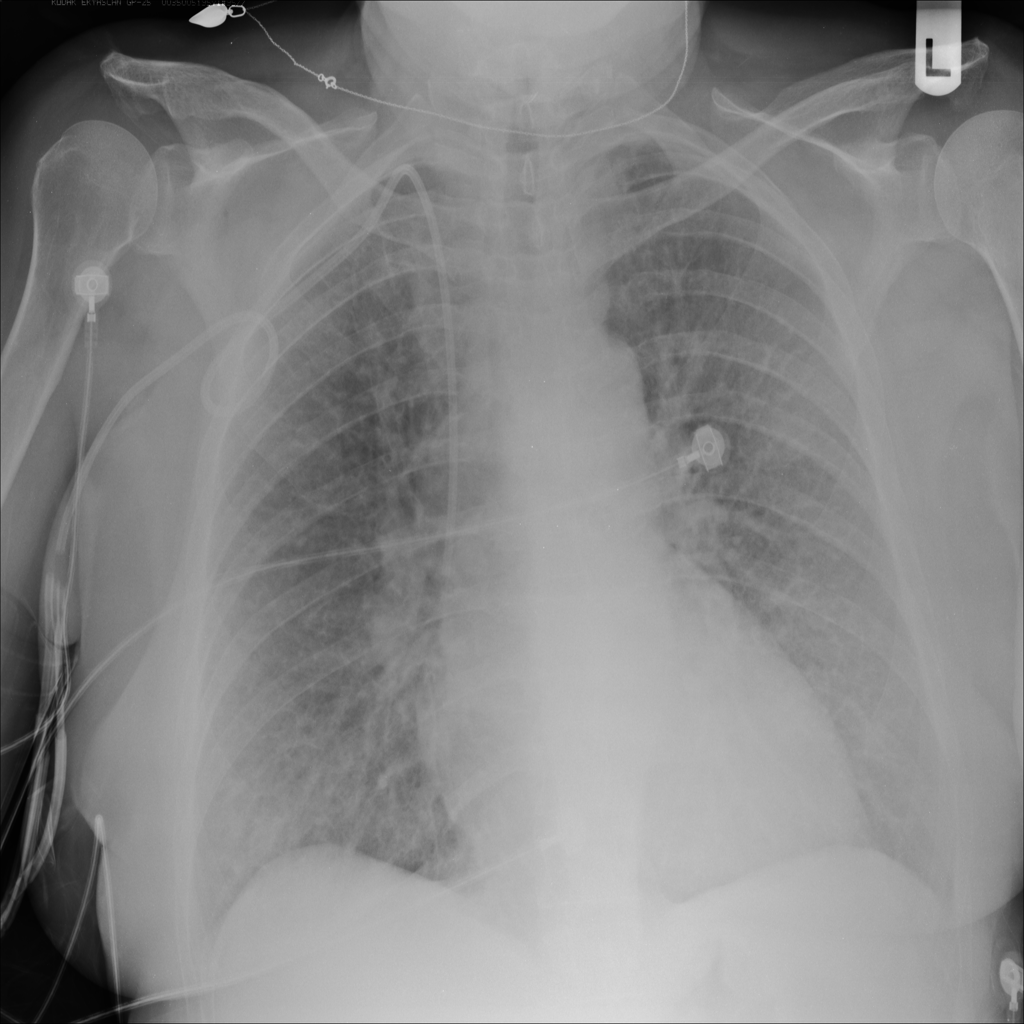

PAT-5B86 · IMG-009Edema

PAT-5B86 · IMG-009

PA